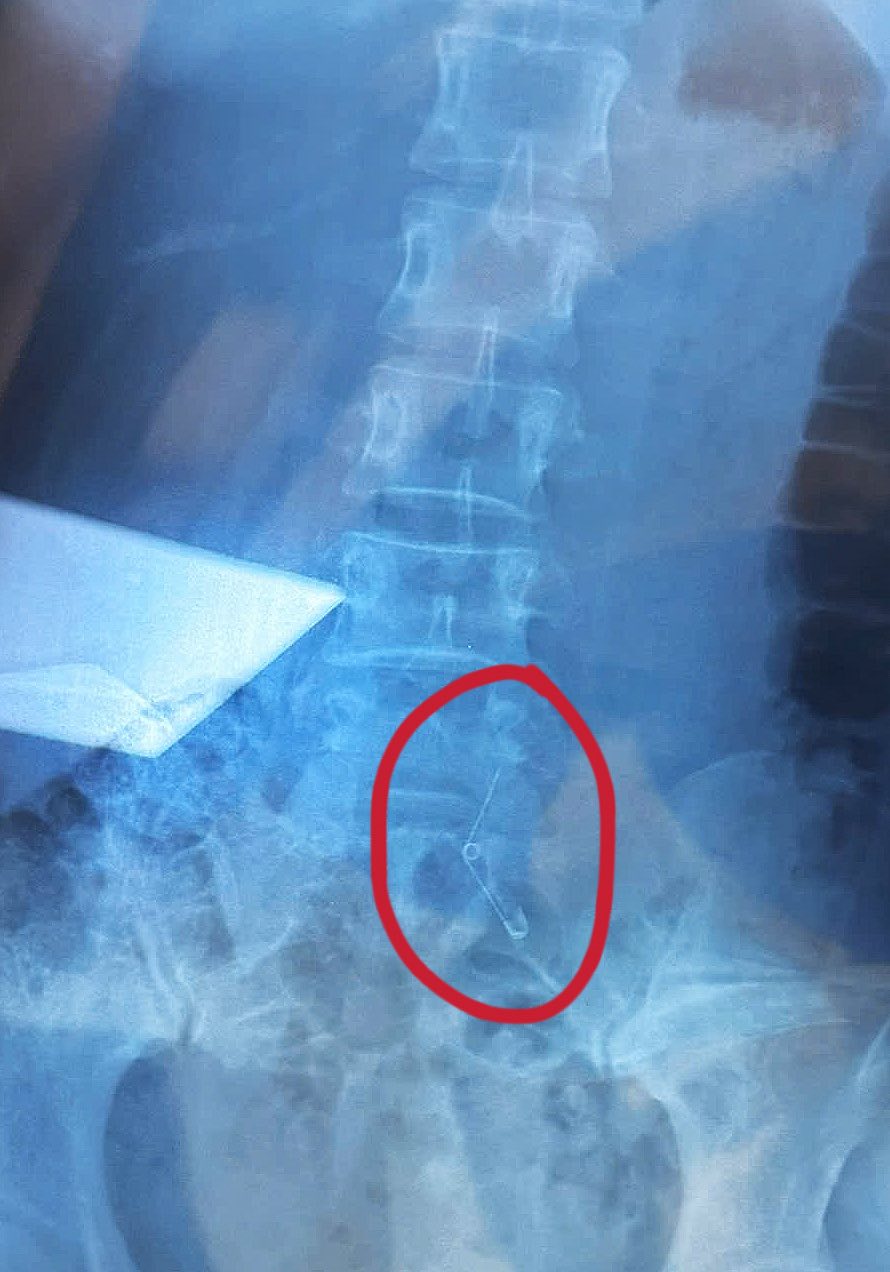

Theo đó, vào tối 26/9, Vân Anh cùng nhân viên công ty ở TP.HCM đi ăn ốc. Đang ăn, cô cảm thấy nuốt nghẹn nghẹn và nhận ra mình không còn cầm kim băng - vật dùng để khều ốc trên tay nữa. Sau đó Vân Anh được đưa đi cấp cứu và mất 6 tiếng để mổ lấy kim băng ra.

Vân Anh Scarlet khi ở bệnh viện và ảnh chụp X-quang chiếc kim băng

Vết mổ và cận cảnh chiếc kim băng sau khi được lấy ra

Ở phần bình luận cô giải thích thêm rằng vì không nội soi thực quản được nên bác sĩ quyết định mổ. Hiện tại, tình hình của cô đã ổn định hơn, đáp lời hỏi thăm của mọi người: “Ăn ốc 2 triệu, tìm kim 70 triệu”.